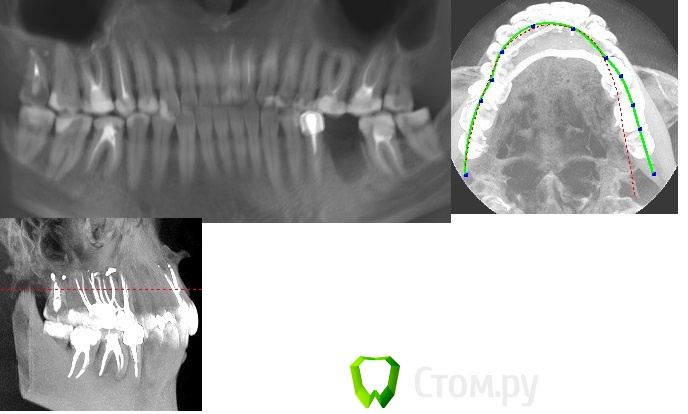

КТ:                                                                                                                                                                       https://cloud.mail.ru/public/772b1feeef54%2FiCATVision%20CD%20__%20(G).zip

1. Для того, чтобы понимать, какой метод восстановления предпочтительнее в каждом отдельном случае, необходимо видеть зуб. Нужно фото зуба/зубов без пломб, демонстрирующие остаточные твердые ткани зуба/ов.  В данном случае ОПТГ - лишь отдаленный помощник, а на КТ фонят рентгеноконстрастные материалы, искажая картину.